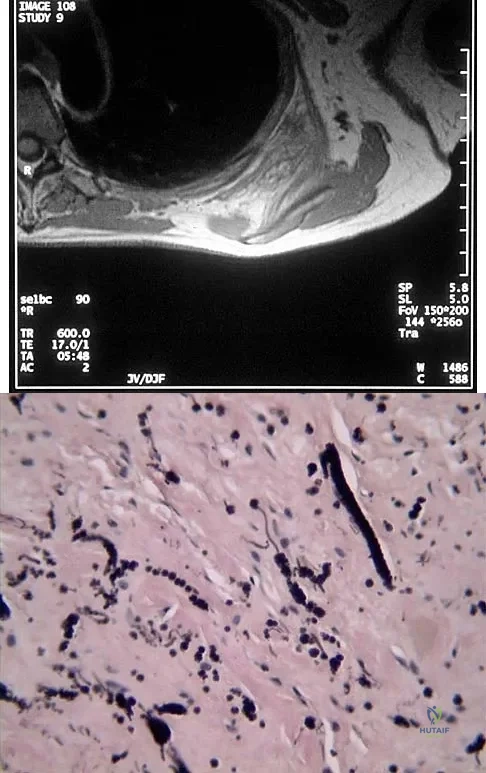

Question 13:

A 58-year-old woman has had a painless periscapular mass for the past year. An MRI scan and biopsy specimen are shown in Figures 4a and 4b. What is the most likely diagnosis?

Correct Answer: Elastofibroma

Explanation:

Elastofibroma is a rare tumor that most commonly occurs in adults who are older than age 55 years. The lesions usually grow between the chest wall and the scapula, and 10% are bilateral. Histologic analysis shows that they are composed of equal amounts of elastin and collagen with occasional fibroblasts. Briccoli A, Casadei R, Di Renzo M, Favale L, Bacchini P, Bertoni F: Elastofibroma dorsi. Surg Today 2000;30:147-152.